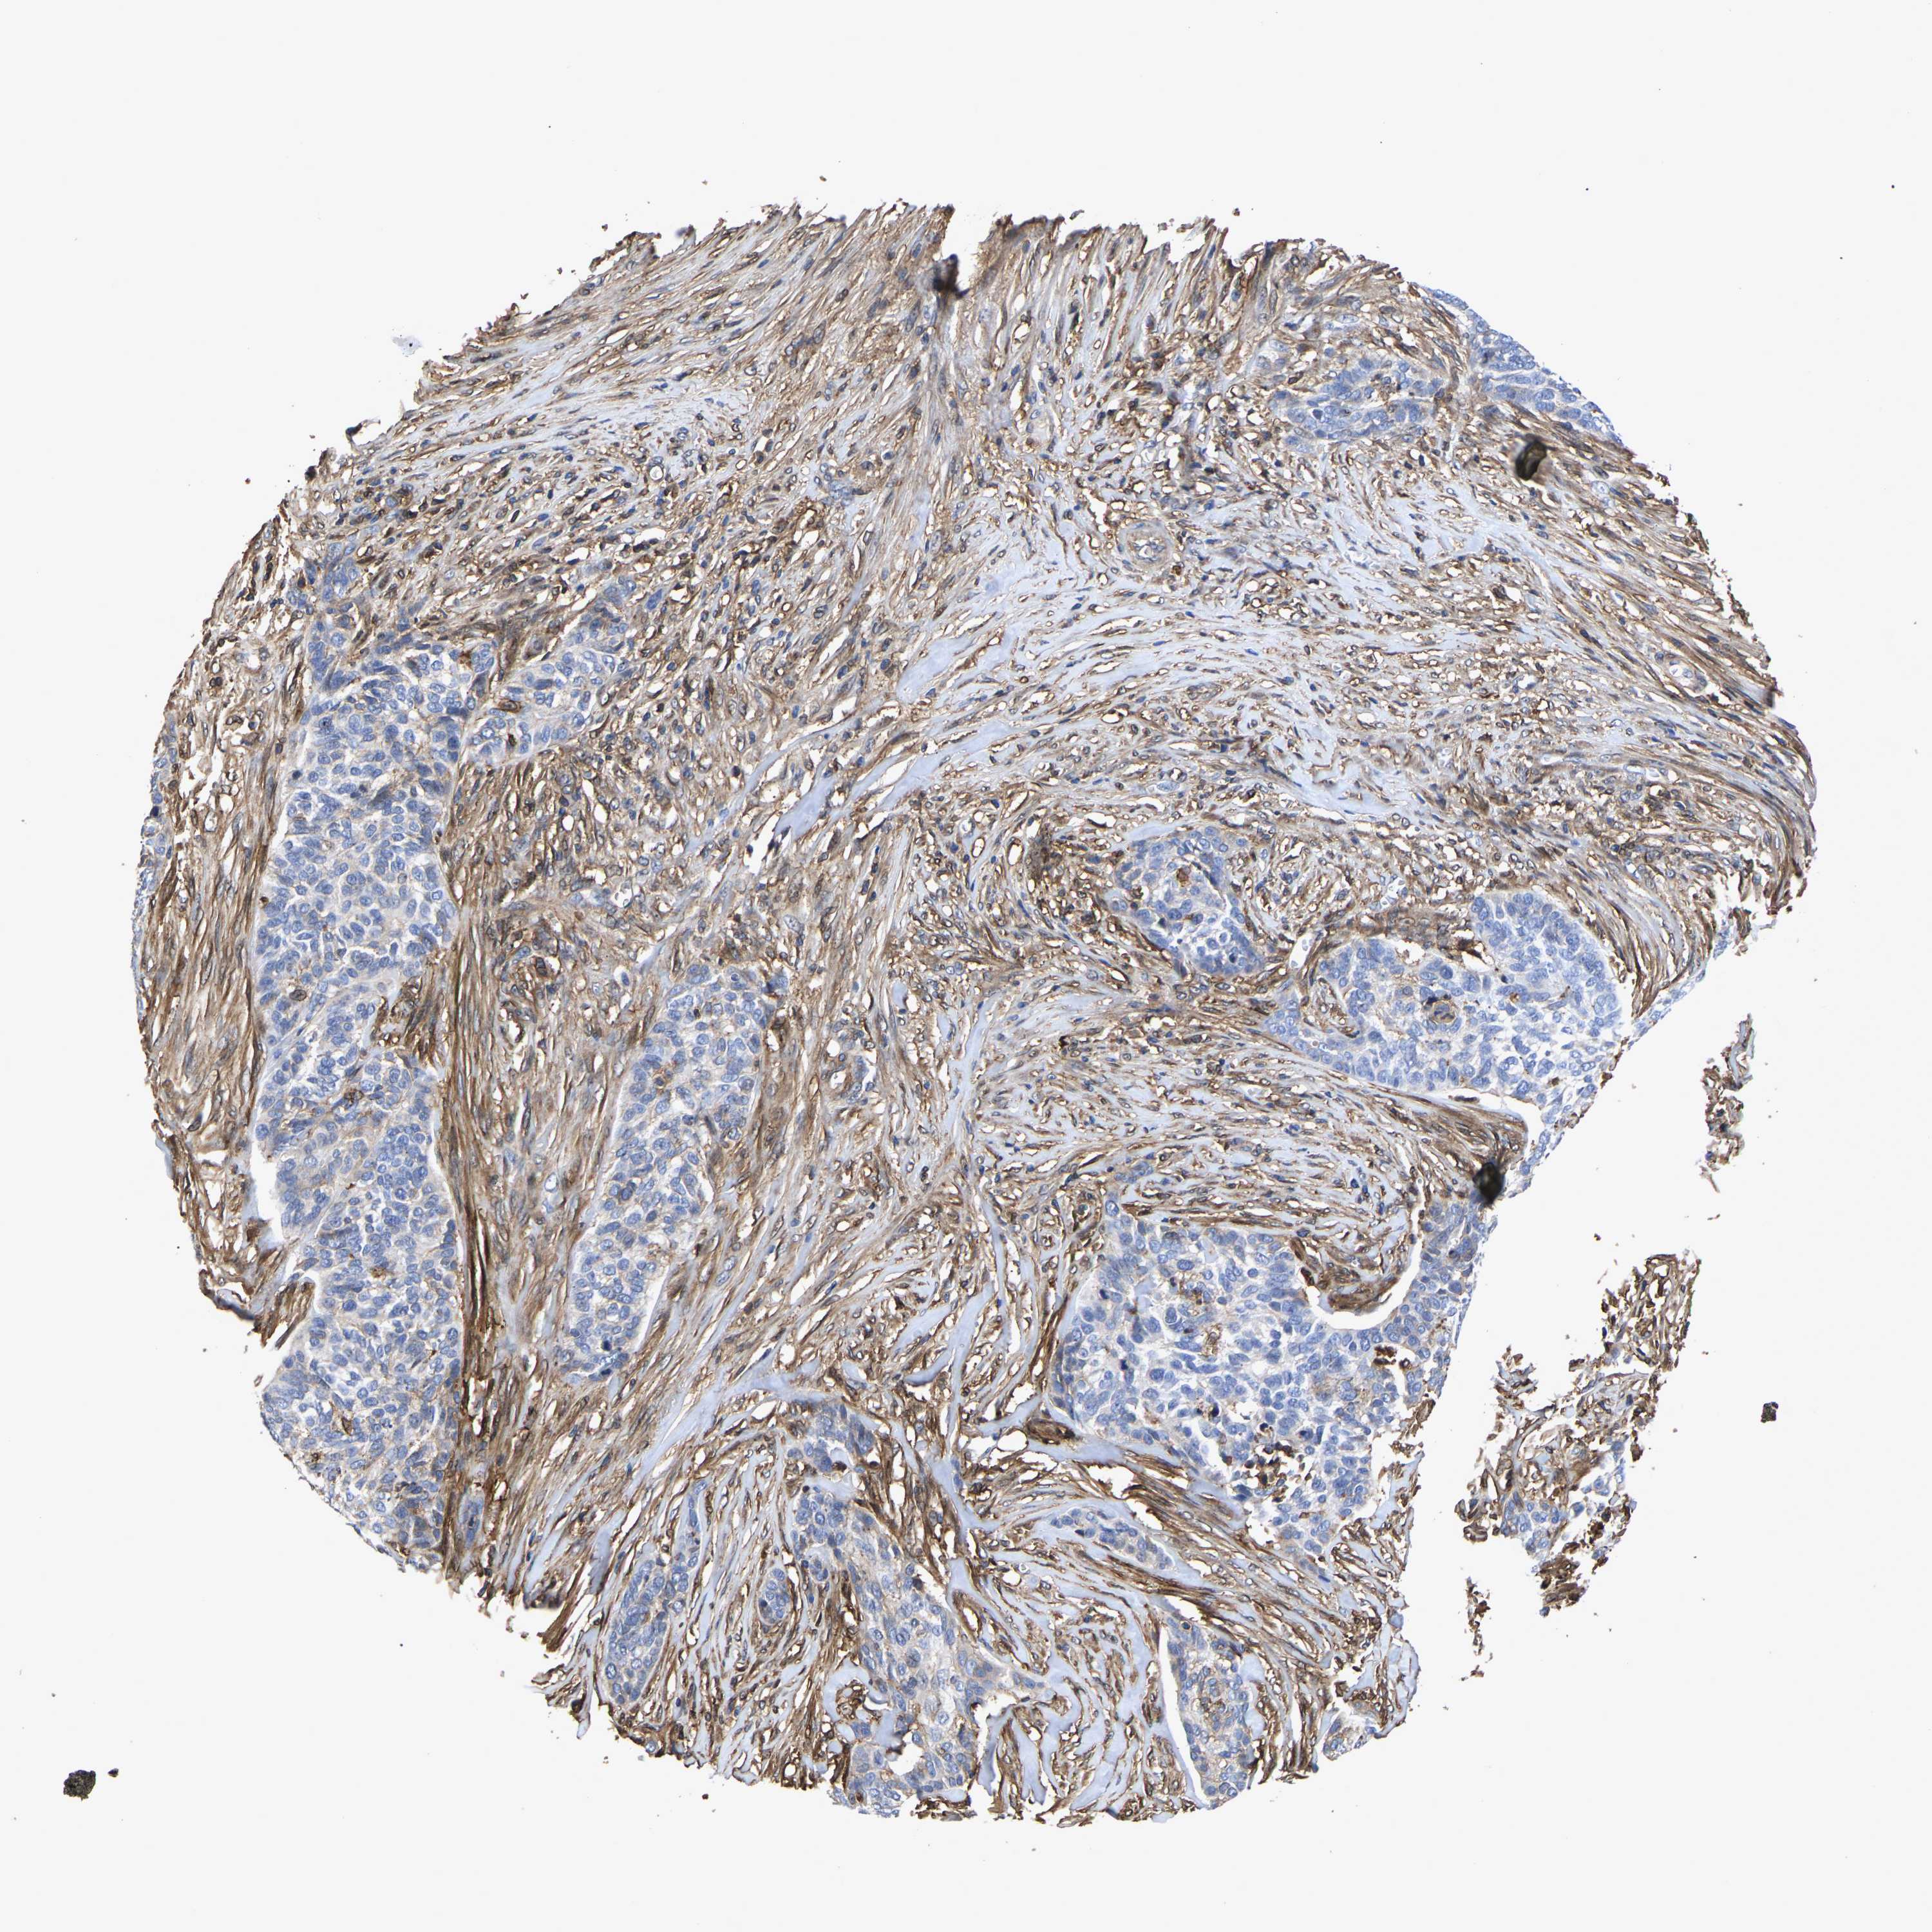

Basal cell and squamous cell cancer

SKIN CANCER - Protein expressioni

A mouse-over function shows sample information and annotation data. Click on an image to view it in a full screen mode. Samples can be filtered based on level of antibody staining by selecting one or several of the following categories: high, medium, low and not detected. The assay and annotation is described here.

Antibody stainingi

Antibody staining in the annotated cell types in the current human tissue is reported as not detected, low, medium, or high, based on conventional immunohistochemistry profiling in selected tissues. This score is based on the combination of the staining intensity and fraction of stained cells.

Each image is clickable and will lead to virtual microscopy that enables deeper exploration of all samples and also displays staining intensity scores, fraction scores and subcellular localization as well as patient and tissue information for each sample.

Antibody HPA018844

Staining

High

Intensity

Strong

Quantity

>75%

Location

Nuclear

Basal cell carcinoma